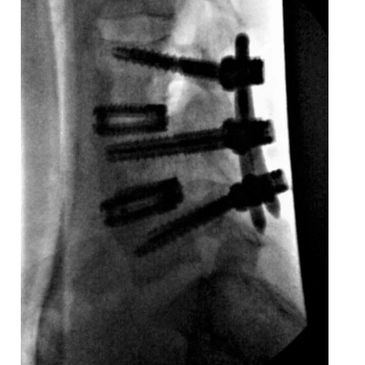

Spine23's patented wire screw technology allows the smallest incision profile for lumbar pedicle screw fusion and TLIF. Xtreme™ TLIF (1 and 2 levels) can be done through a single dime sized midline incision or bilateral dime sized Wiltse incisions.

Spine23's Xtreme™ MIS lumbar fusion allows 1 and 2 level lumbar fusions and TLIF surgeries to be performed safely in the outpatient setting and ASC. Xtreme™ MIS can unleash the full potential of recent advancements in anesthesia as well as expandable cage technology, robotics, and endoscopy.

Spine23 's Xtreme™ MIS posterior lateral lumbar fusion perfectly complements anterior (ALIF) and lateral (LLIF) approaches for interbody cage placement. One and two level pedicle screw fusions can be performed through a single midline or bilateral Wiltse incisions as small as 12mm.